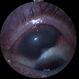

- ciliary body mass, immersion ultrasound, cystic lesion

- Immersion ultrasound of mass shows cystic lesion 11mm in diameter